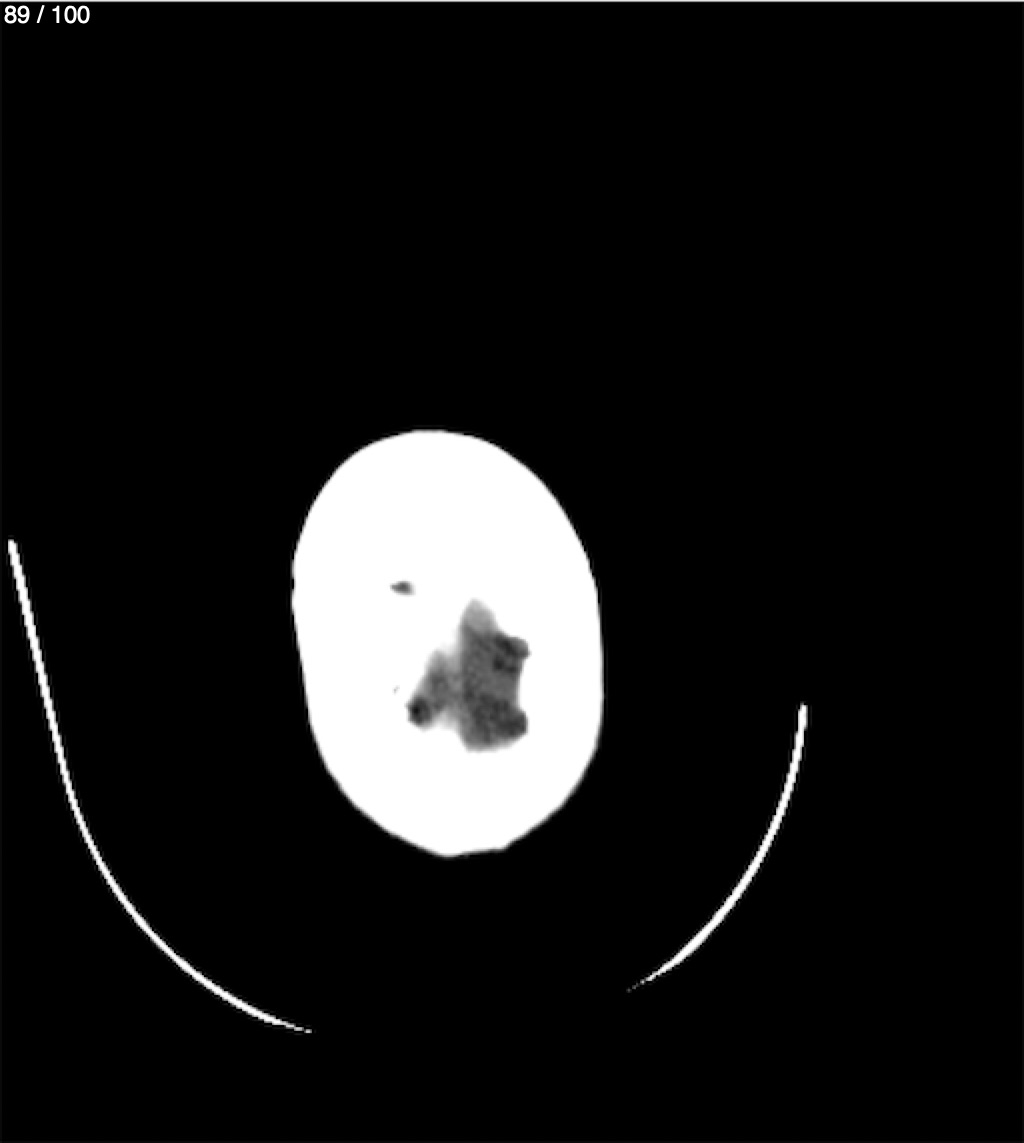

Valentin Perez Gomez 69A - T.C Craneo